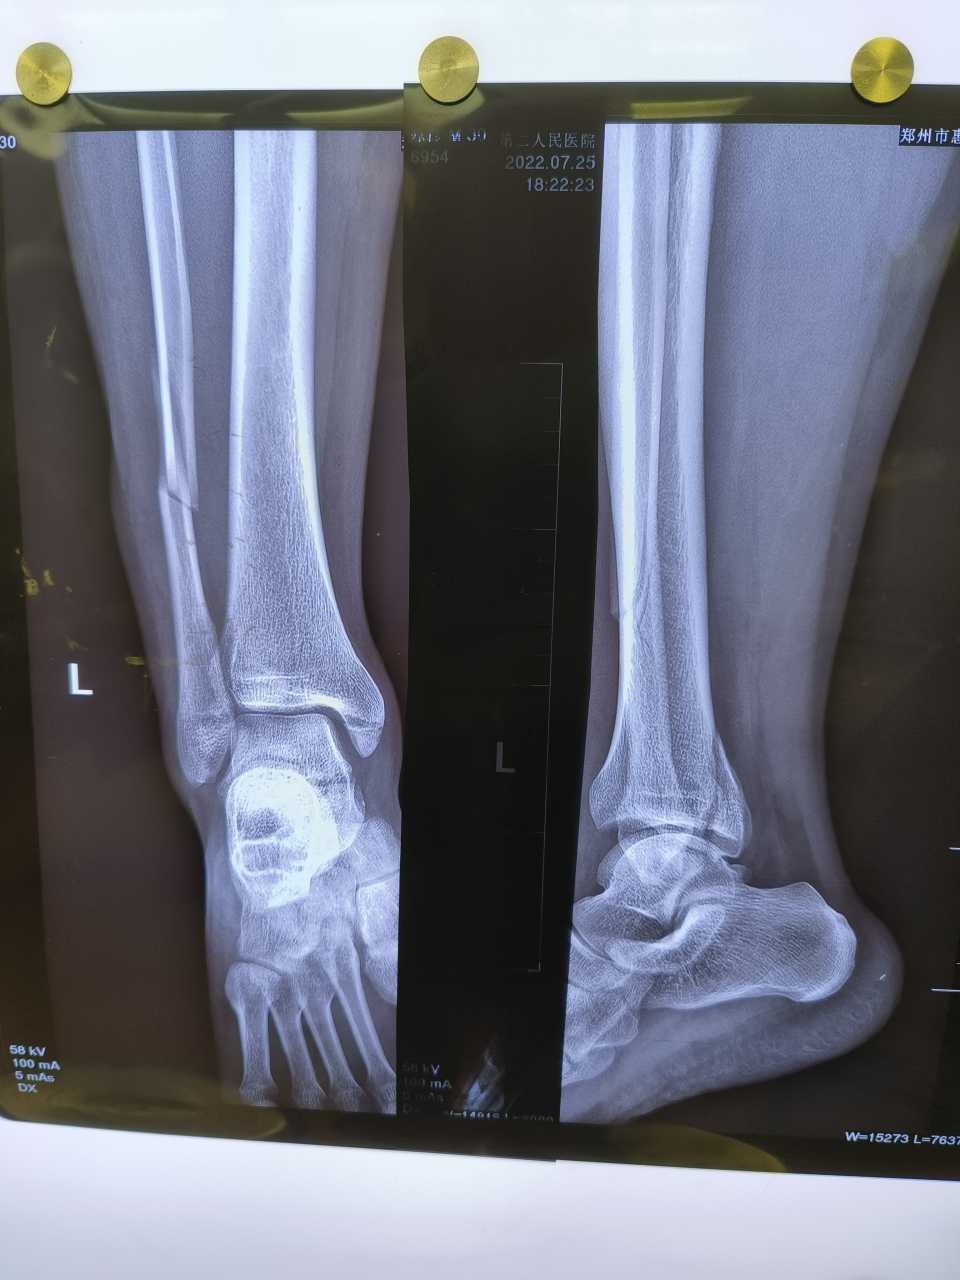

中年男性踝关节骨折旋前外旋iv

典型的#踝关节# #骨折# 旋前外旋4度,完美解剖复位.祝患者早日康复!